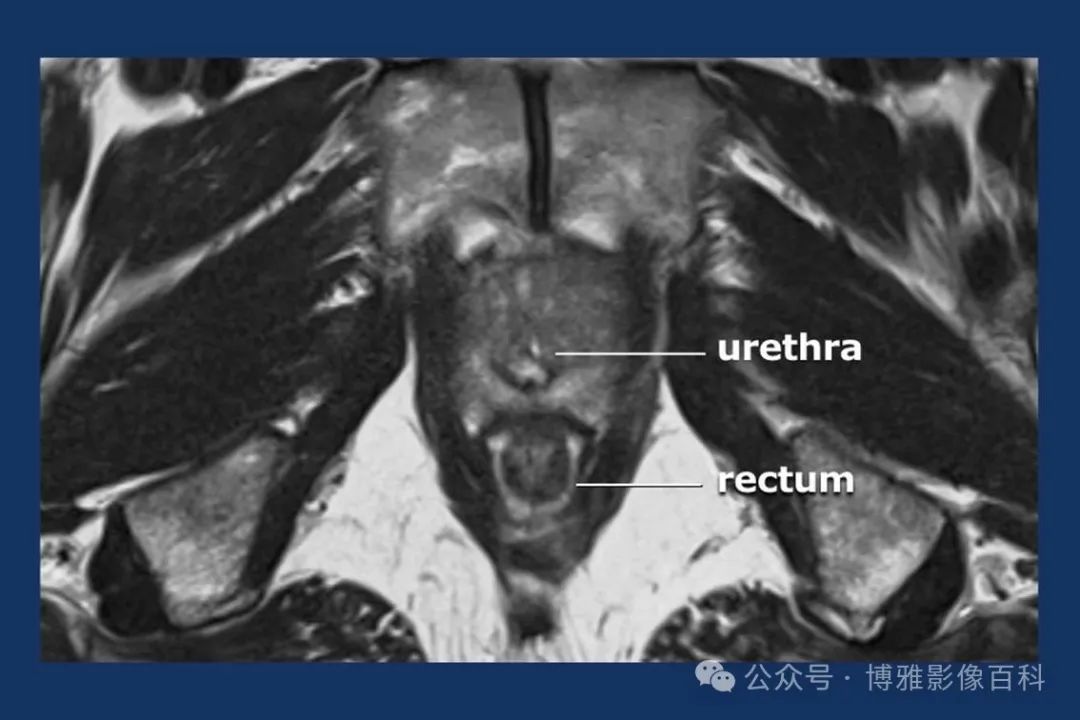

MR 解剖学

前列腺良性增生患者的轴向T2 图像,其他方面正常。外周带是一薄层均匀的高信号,边界清晰连续性的低信号包膜。移行带通常表现为不均匀中等信号,病灶被边界清楚的BPH良性前列腺增生结节所取代。精囊具有均匀T2高信号。未见淋巴结肿大。